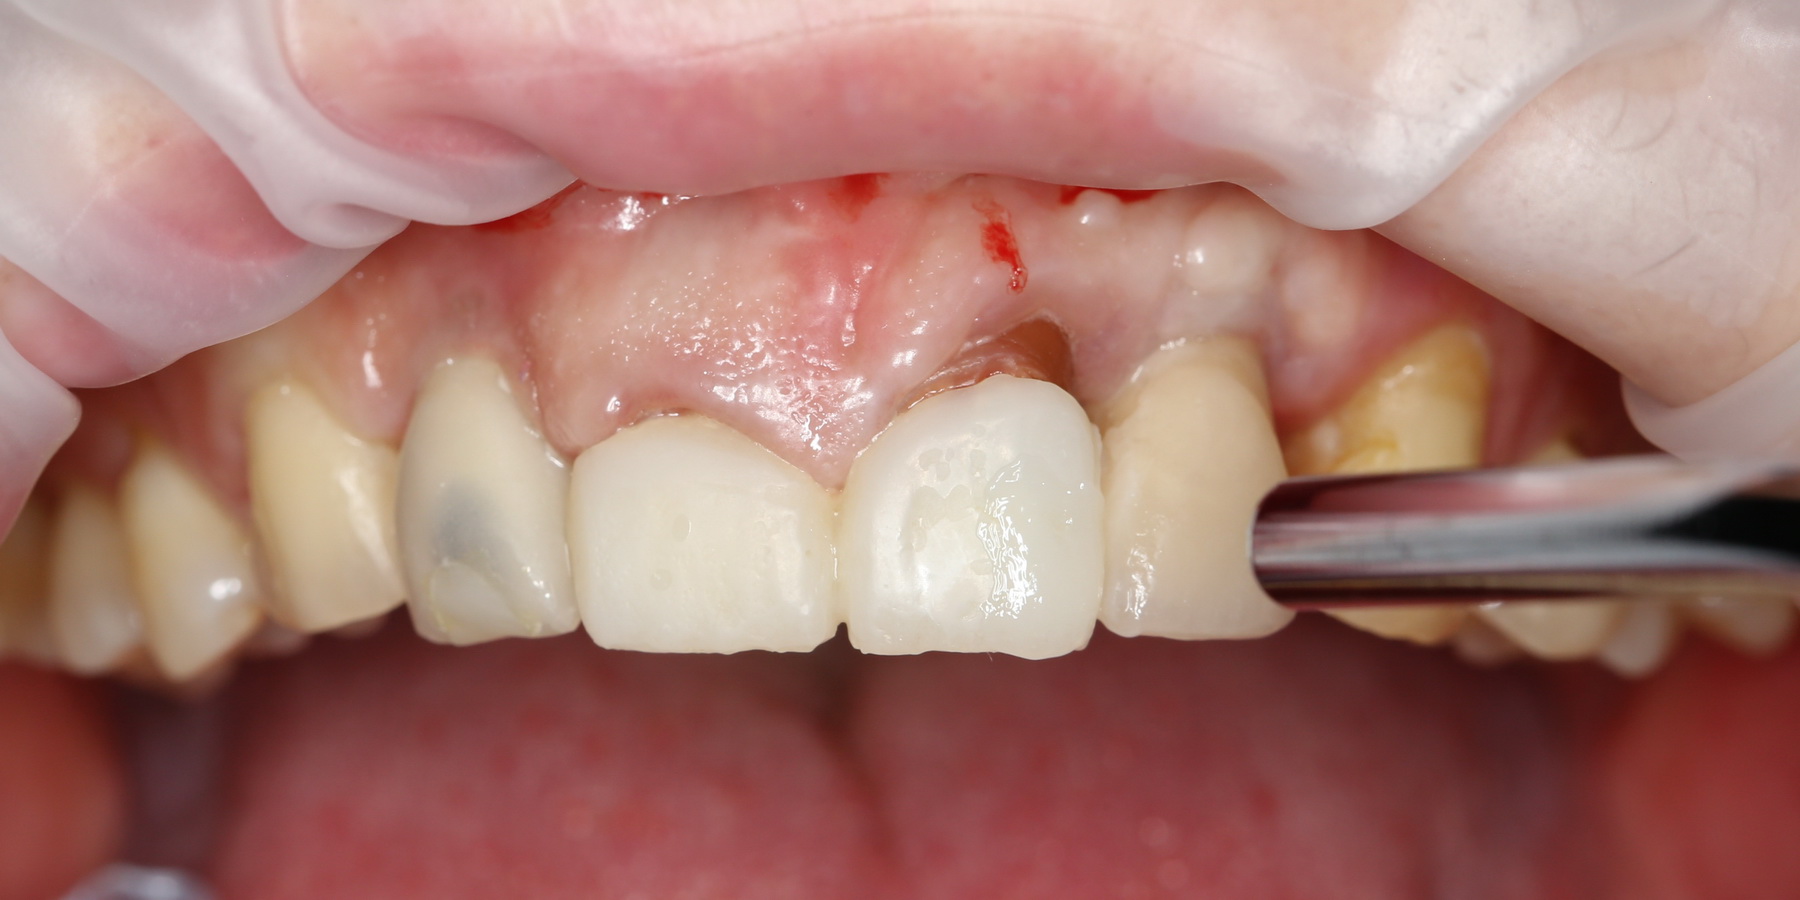

Давайте внимательно посмотрим на состояние лунок центральных резцов после удаления:

Приемлемый фенотип (сочетание толщины и ширины участка жевательной десны) — это, конечно, приятно. Но гораздо важнее сосредоточиться на рисках, их на этот момент два:

— травматическое повреждение слизистой, вызванное удаление зубов связано с тем, что при хроническом воспалении слизистая оболочка теряет эластичность, поэтому легко рвётся. Такая ситуация создаёт серьёзную угрозу эстетическому результату лечения, в зависимости от того, насколько быстро десна придёт в норму.

— как и предполагалось после КЛКТ, утрата костной стенки привела к тому, что десна провалилась в просвет лунки левого центрального резца. Это еще больше усугубляет клиническую ситуацию.